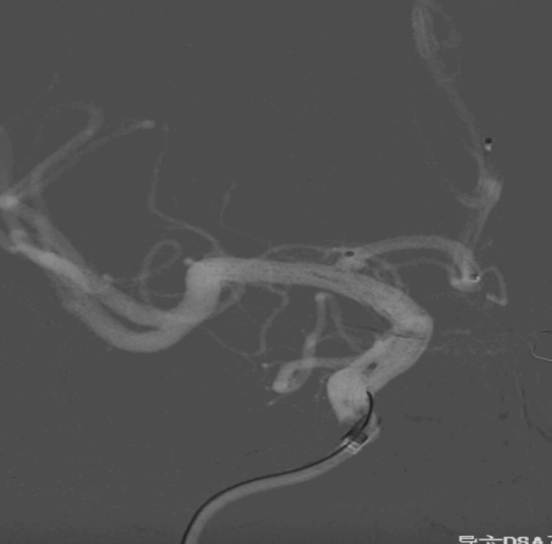

工作位正位造影(图片)

工作位正位造影(视频)

6F Envoy DA在泥鳅导丝辅助下超选至右侧颈内动脉海绵窦段后膝。

继续填入Target 1.5/2弹簧圈成篮,后完全释放支架,其近端位于颈内动脉分叉处,远端位于A1远端。

术后正侧位造影:Raymond Ⅲ级